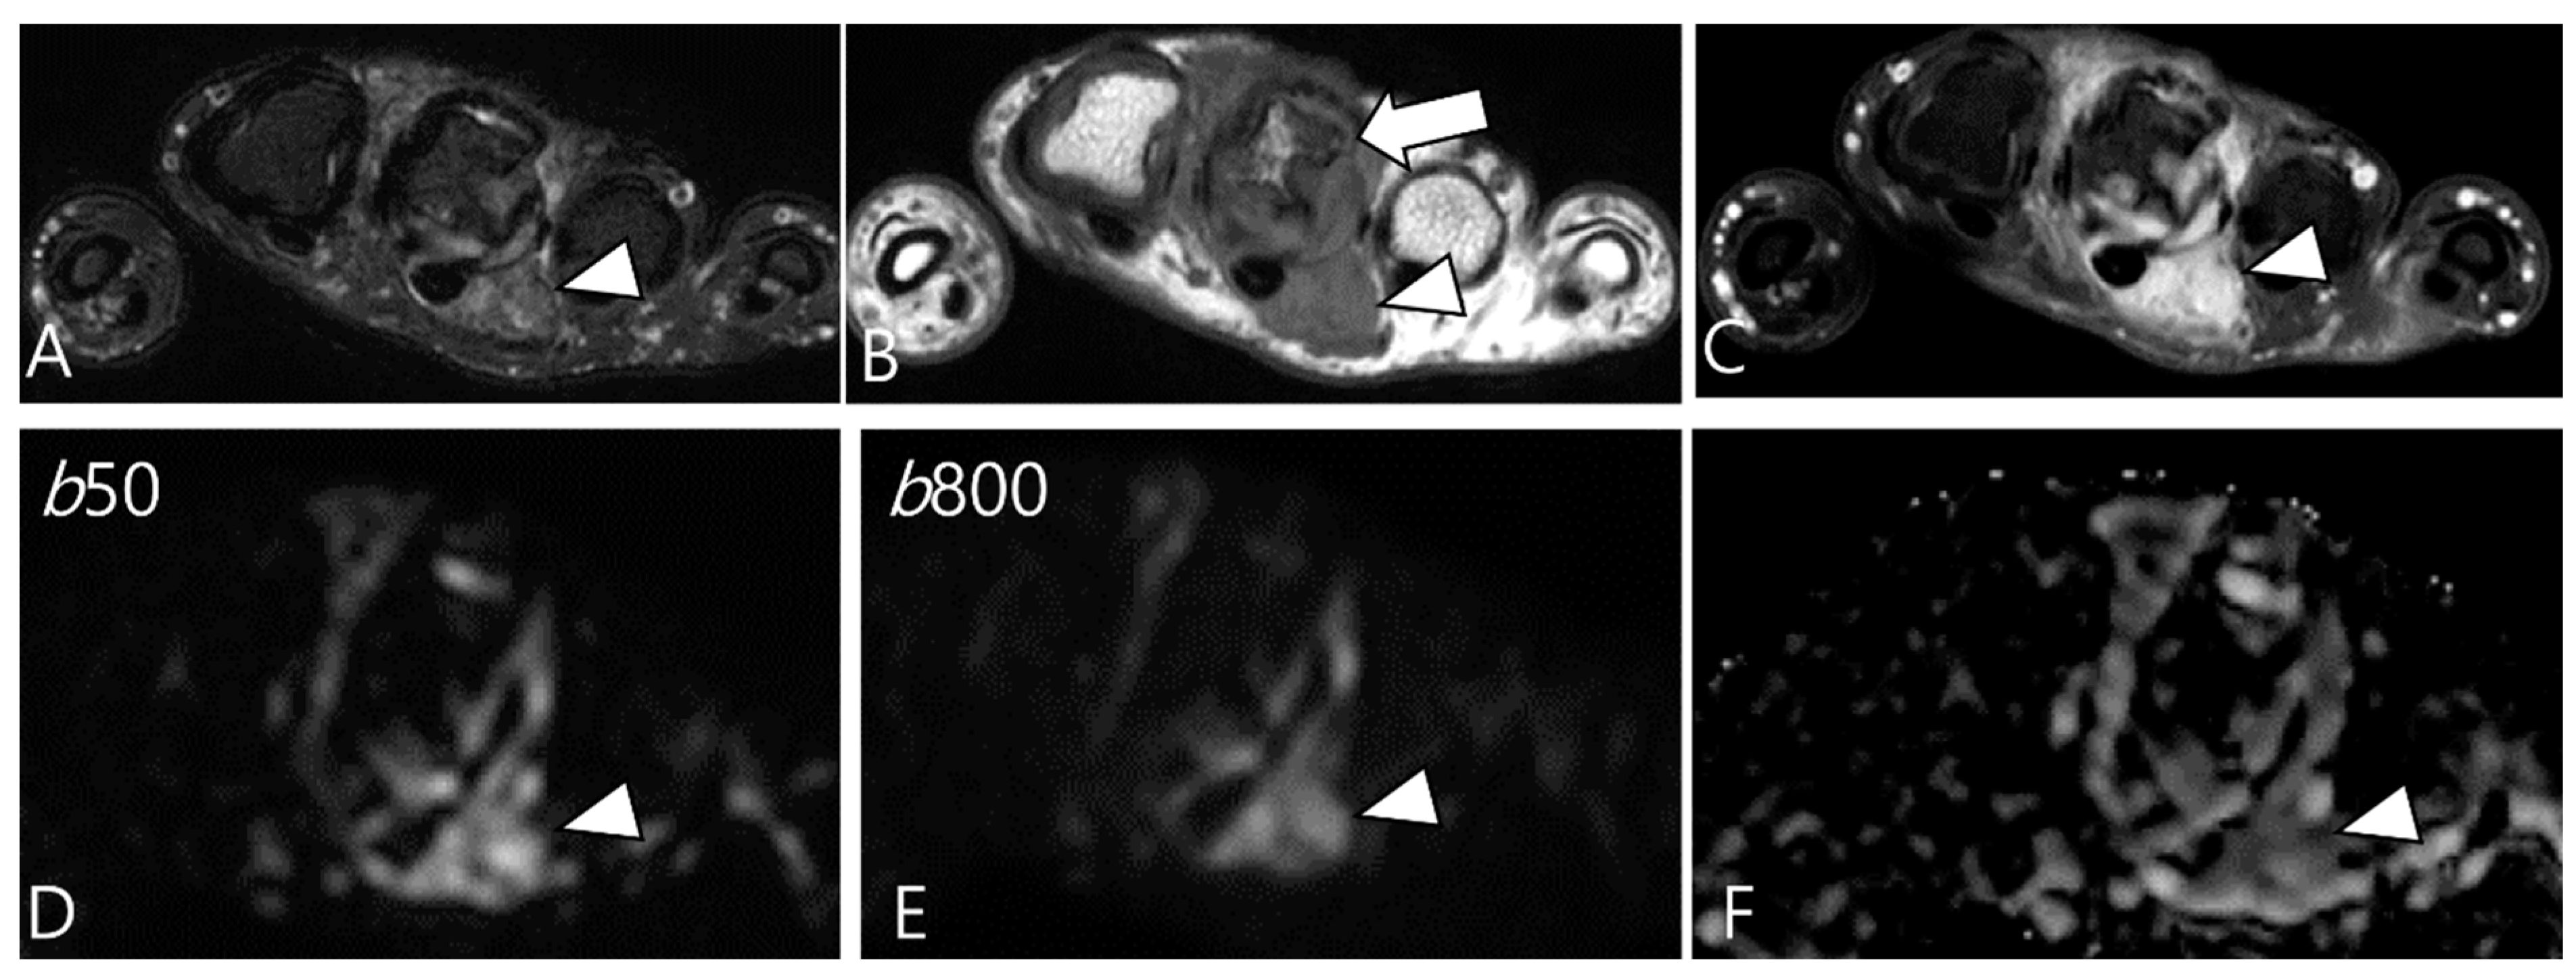

3.2. Differential Diagnoses of Extra-Articular D-TSGCT